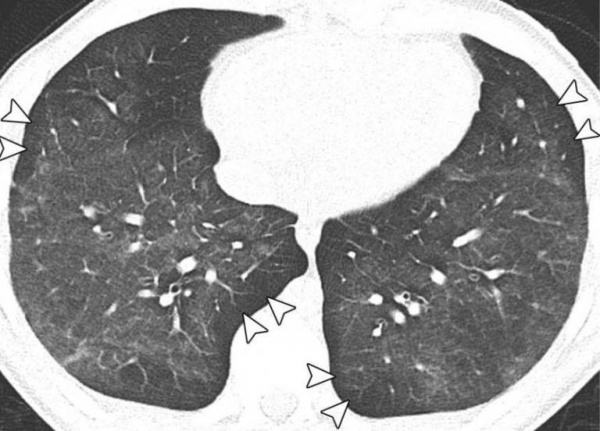

• Рентгенодиагностика. В 90% случаев на рентгенограммах легких видны двусторонние инфильтраты. КТ грудной клетки показывает двусторонние патологические изменения в легочной ткани по типу матового стекла, преимущественно в нижних долях. Кроме того, могут определяться плеврит, пневмоторакс и пневмомедиастинум. Однако эти признаки неспецифичны и проявляются при различных заболеваниях.

Компьютерная томография грудной клетки. Двусторонняя непрозрачность в виде матового стекла.